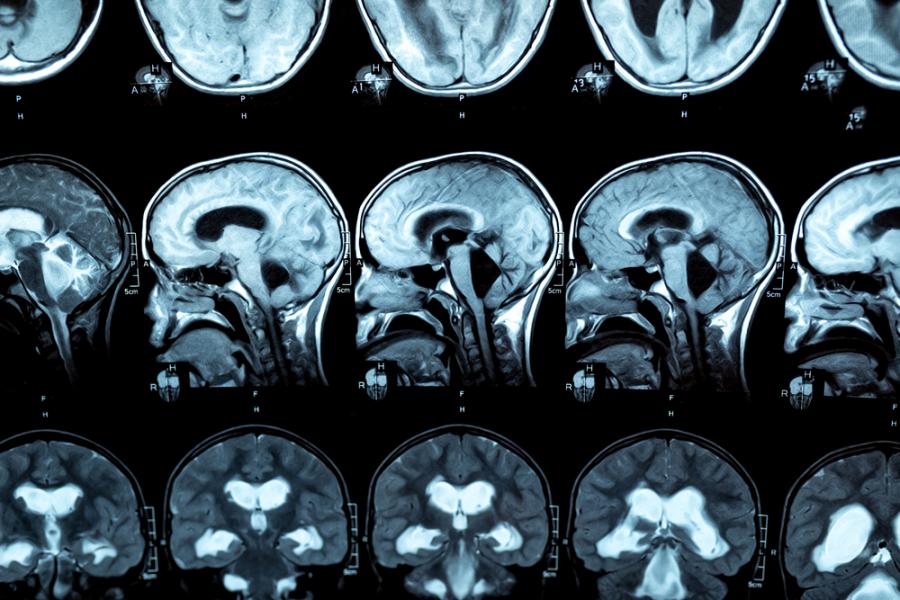

Екипът прави спинална пункция, за да анализира мозъчно-мозъчната течност на пациентите. Получените резултати са изненадващи - пациентката няма почти никакъв В12 в течността, която се използва в мозъка и централната нервна система, което предполага, че нещо му пречи да премине през кръвно-мозъчната бариера.